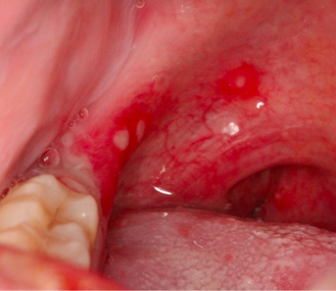

鹅口疮鹅口疮是一种由白色念珠菌引起的口腔黏膜的炎症,在婴幼儿中常见。

宝宝颊粘膜、舌头或口咽部不规则白色凝乳状物质。白膜不容易擦掉,强行擦的话,会露出下面红色粘膜,甚至还会流血。

宝宝可能由于疼痛而拒绝进食和吞咽,或不明原因哭闹。

奶块跟鹅口疮看起来有一些相似,用湿棉签轻轻擦拭,如果白色块状物消除的话,就说明是奶块;如果擦除有困难或者留下了红色创口的话,就说明宝宝得了鹅口疮。

图片来源:[2]